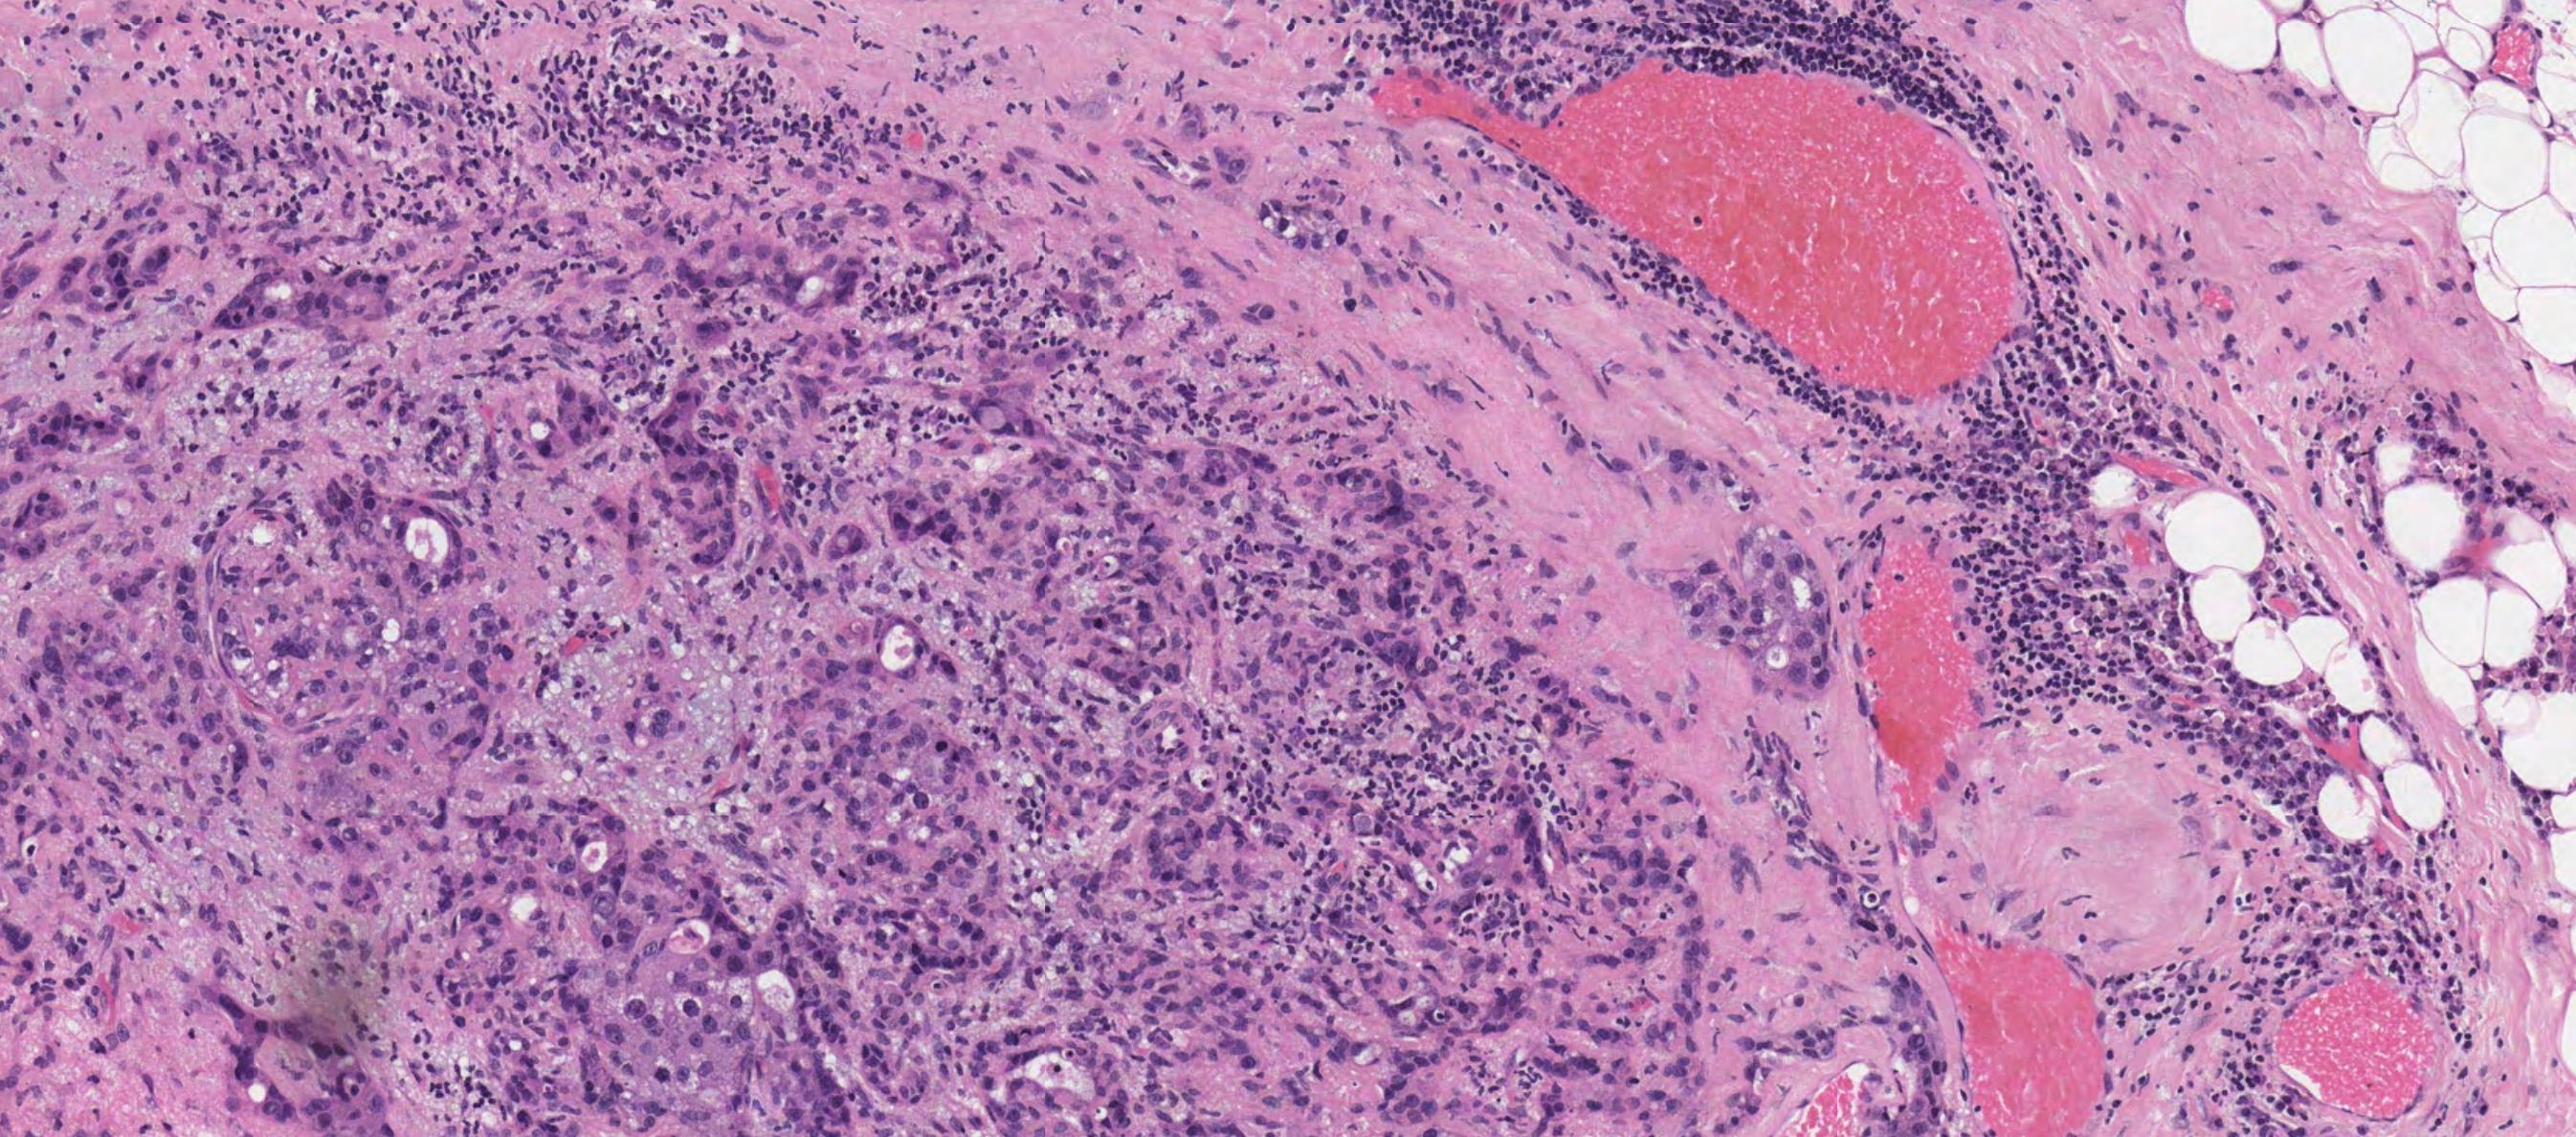

Case 10 66-year-old Excision Of Tumour Tongue / Floor Of Mouth.

Case 10 Diagnosis

Mucosal melanoma

• 80% of head and neck MM- nasal cavity, septum, maxillary sinus • In the oral cavity-maxillary gingiva and palate • Flat pigmented lesions • Tumour cells are polymorphic • Lentiginous/pagetoid growth pattern • All head and neck mucosal MM are T3–4 and stage III-IV • T3 Tumour limited to the epithelium and/or submucosa (mucosal disease) • T4a Tumour invades deep soft tissue, cartilage, bone, or overlying skin • Oral pigmented patches DD • Melanotic macule • Smokers melanosis • Amalgam tattoo • Naevi